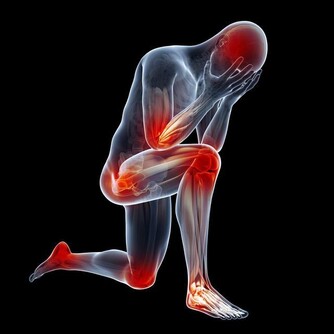

滿頭大汗伴四肢發涼,可能心臟病

在沒有明顯原因的情況下,如果突然滿頭大汗,甚至導致渾身濕透,臉色蒼白或灰白,四肢發涼,並伴有心前區絞痛、肩膀放射性疼痛,應馬上懷疑心絞痛、心肌梗死等心臟病發作的可能。

心臟病發作時,血管迷走神經過度反應、冠狀動脈出現痙攣,就會導致出汗、胸痛,緊接著可能出現心率和血壓驟然下降。

心臟病患者應隨身帶好急救藥以防萬一,一旦發作,最好平躺休息,並把衣領扣子解開,情況嚴重時馬上撥打急救電話。